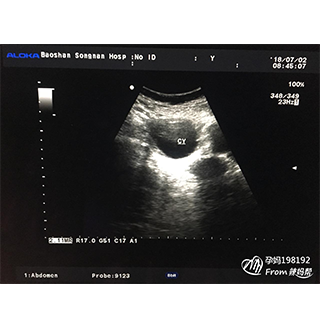

NT(nuchal translucency),即頸項(xiàng)透明層,是指胎兒頸椎水平矢狀切面皮膚至皮下軟組織之間的大厚度。NT檢查又稱頸后透明帶掃描,是通過B超手段測量胎兒頸項(xiàng)部皮下無回聲透明層厚的部位,用于評估胎兒是否有可能患有唐氏綜合征的一種方法。

顯示的是一個頸后透明帶正常寶寶,得病的風(fēng)險較低。